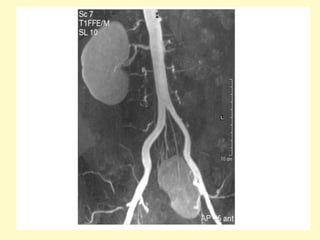

Renal agenesis, Coronal maximum intensity projection (a) and volume

rendering (b) demonstrate absence of the left kidney and

compensatory hypertrophy of the right kidney, which shows a

cortical cyst, the left main renal artery was absent